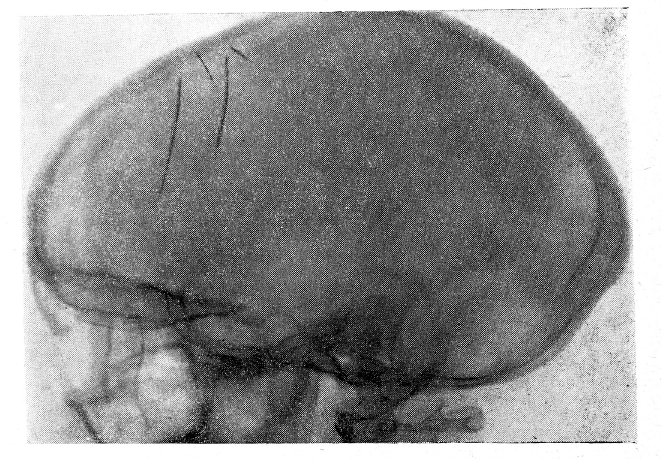

Рис. 2

Рентгенография от 17/IV-59 г. (рис. 1 и 2). На рентгенограмме черепа в двух проекциях определяются две швейные иглы, располагающиеся почти вертикально, внутри мозговой ткани — в области венечного шва и на полсантиметра вправо от срединной сагиттальной плоскости. Верхние концы игл (с ушками) располагаются вблизи от внутренней пластинки свода черепа. Длина игл — около 5 см. В этом же отделе черепа под углом к описанным иглам располагаются два отломка игл с заостренными концами длиною около 1,5 см. Костных дефектов в своде черепа не найдено.